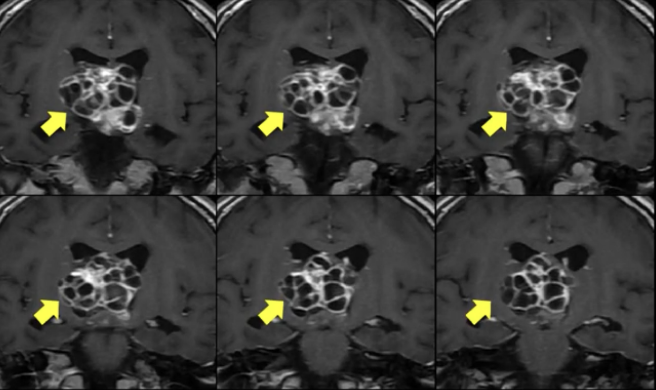

且不说它内含的十几个“魔眼”般狰狞的囊肿,像石榴籽一样相互包裹、挤压,直插大脑核心区;单就它的大小,直径超过4厘米,挤满整个脑深部的中央区域,也是闻所未闻,国内外文献罕见有过这个位置这么大肿瘤的报道。

术前核磁共振显示脑深部巨大肿瘤,压迫下丘脑和脑干